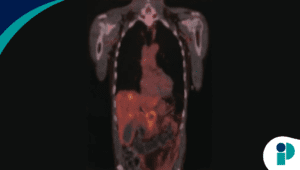

Tras un tratamiento de soporte que permitió elevar su nivel de plaquetas a 23 × 10⁹/L, el equipo médico procedió con una gastroscopia. El examen reveló más de 50 lesiones angioectásicas (malformaciones vasculares) con sangrado activo en el tracto gastrointestinal. Gracias a un procedimiento de coagulación con plasma de argón, fue posible controlar los sangrados, lo que permitió estabilizar a la paciente y darle el alta con un pronóstico favorable.